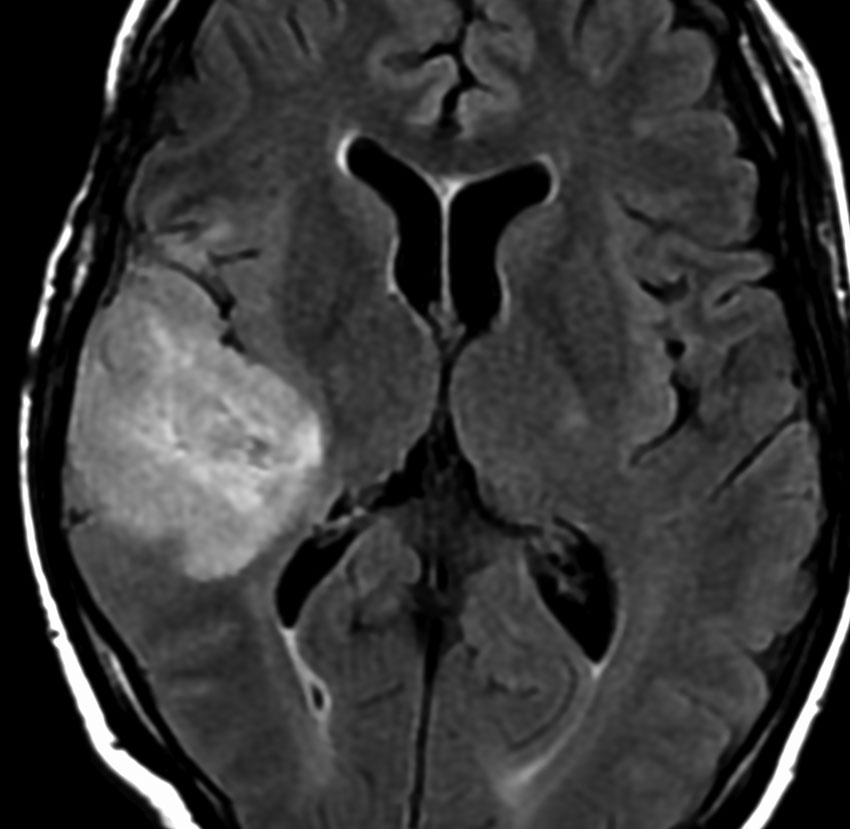

症候性てんかんのみで発症した右側頭葉と島回のグレード2オリゴです。左のT2,中央のフレアではグレード2びまん性星細胞腫と鑑別はできません。認知機能などは正常でした。

何と言っても診断的価値があるのは 石灰化 carcification です。左のCTの中央にみえる白い部分が石灰化です。この程度の石灰化でも診断的な価値があります。1p/19q codeletionがあるオリゴでした。病理では,均一な小型の円形核を有する細胞と多数の毛細血管 chickin-wire network がみられます。部分摘出後,放射線治療とテモゾロマイド化学療法でコントロールできています。